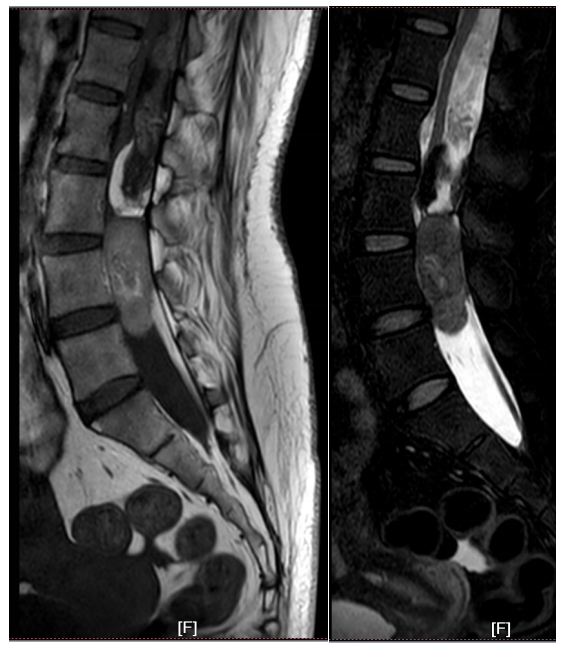

病例3:女性,31岁

患者以“腰部疼痛半月,加重3天”为主诉入院,自诉腰部疼痛,休息后无缓解。专科查体:腰部压痛及叩击痛+,双下肢小腿肌群肌力Ⅳ级+,感觉正常,无明显病理征。

结合患者影像学资料,女性,髓外硬膜下病变,病变位于胸腰段,节段较长,位于圆锥附近,T1、T2混杂信号,并合并有脂肪信号,患者症状较轻,病情发展时间较长,倾向于畸胎瘤可能。

行“胸腰椎椎管内肿瘤切除+钉棒内固定术”,术后腰部疼痛症状明显缓解,下肢肌力恢复正常。